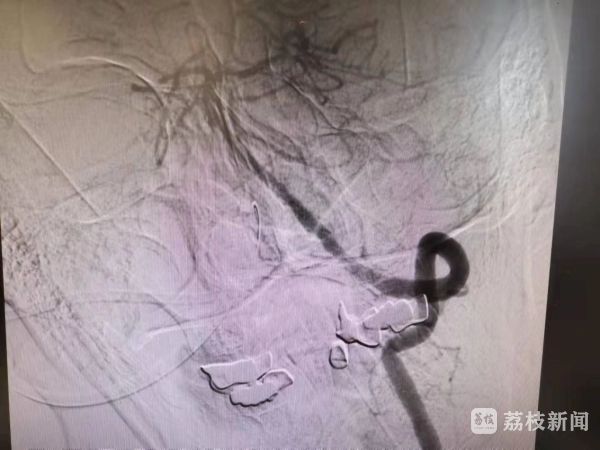

人的基底动脉,直径仅4毫米左右,在如此细小的血管内操作导丝,难度胜过绣花。但在文立利主任那着手成春的技术下,那一条导丝如同泥鳅一般,灵活的在患者的血管中穿行,拐过一个又一个弯,迅速到达了患者血管堵塞部位。

在文立利主任的精妙操作,以及助手陈灿医生的熟练配合下,当血栓随着支架被一把拉出时,所有人的心中都长舒了一口气——王先生基底动脉的血流恢复了!

虽然血流恢复了,但王先生基底动脉中段仍有重度狭窄,需要进行基底动脉狭窄部位球囊扩张及支架置入。支架置入后,王先生基底动脉的血管形态终于恢复了正常!